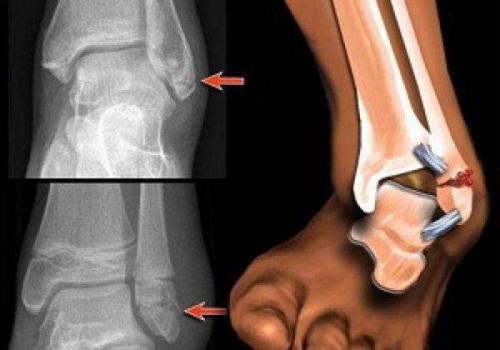

Остеоартроз левого(справа на снимке) голеностопного сустава

Для артрозов характерны такие изменения в голеностопном суставе:

- дегенерация хрящей и ухудшение их амортизирующей функции;

- асептическое воспаление и отек синовиальной оболочки;

- размягчение и изъязвление хрящей, обнажение подлежащих костей;

- субхондральный склероз костной ткани;

- сужение суставной щели и формирование костных экзостозов;

- гипотрофические и фиброзно-склеротические изменения параартикулярных тканей;

- прогрессирующая деформация сустава с нарушением его функций.